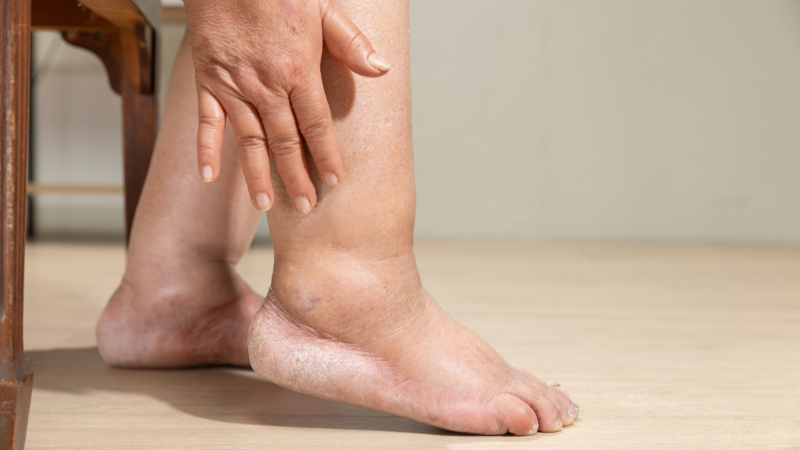

- Schwellung des betroffenen Gelenks und Gelenkschmerzen. Diese Anfälle treten oft plötzlich und meist nachts auf, was die Schmerzen noch intensiver erscheinen lässt. Es gibt verschiedene Formen des Anfalls, wobei besonders der akute Gichtanfall (Gichtarthritis) mit plötzlicher Entzündung einzelner Gelenke wie Rötung, Schwellung und Schmerzen im Mittelpunkt steht. Der Schmerz kann dabei sehr belastend sein und auch die Zehen betreffen.

Häufig werden Gichtanfälle durch schwere Mahlzeiten oder Alkoholkonsum ausgelöst. Interessanterweise sind bei akuten Gichtanfällen nicht immer erhöhte Harnsäurespiegel im Blut nachweisbar, obwohl die Entzündungswerte erhöht sind. Auch die Knie können häufig von Gicht betroffen sein, was zu Schmerzen und Schwellungen in diesen Gelenken führt. Diese widersprüchlichen Befunde können die Diagnose erschweren, weshalb eine gründliche Untersuchung notwendig ist.

Eine chronische Gicht kann zu dauerhaften Gelenkentzündungen und Schäden an inneren Organen führen. Bei unbehandelter Gicht kann es zu chronischen Entzündungen und dauerhaften Gelenkschäden kommen, die die Beweglichkeit stark einschränken. Diese Schäden entstehen durch wiederholte Gichtanfälle und die damit verbundenen Entzündungen.

Ein weiteres Risiko bei unbehandelter Gicht sind Nierensteine, die aus Harnsäurekristallen bestehen. Die Niere spielt dabei eine zentrale Rolle, da sie für die Ausscheidung von Harnsäure verantwortlich ist. Kommt es zu einer Überlastung der Niere oder zu Funktionsstörungen, kann sich Harnsäure ansammeln und die Bildung von Nierensteinen begünstigen. Auch das Risiko für Herz-Kreislauf-Erkrankungen ist bei Patienten mit unbehandelter Gicht erhöht.